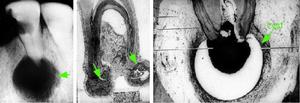

根尖肉芽腫。

根尖肉芽腫病理分析根尖肉芽腫為附著在牙根尖部約綠豆大小的肉芽,因與牙根尖區牙周膜相連,可隨拔牙時一同拔出(圖2)。 鏡下觀察根尖區可見增生的肉芽組織團塊,周界清楚,主要由新生的毛細血管、成纖維細胞和浸潤的各類炎症細胞構成,炎症細胞包括淋巴細胞、漿細胞、巨噬細胞和中性粒細胞(圖3,4)。毛細血管內皮細胞增生腫脹,巨噬細胞吞噬脂質後形成泡沫細胞。可見含鐵血黃素和膽固醇晶體沉積。膽固醇晶體在製片過程中被有機溶劑溶解而呈現針狀透明裂隙,並可引起多核巨細胞反應。 肉芽組織外周常有纖維結締組織包繞。根尖牙骨質和牙槽骨有吸收(圖5)。 根尖肉芽腫內可見增生上皮團或上皮條索,相互交織呈網狀(圖6,7),這些上皮來源於:(1)Malassez上皮剩餘;(2)經竇道口長入的口腔上皮; (3)牙周袋袋壁上皮; (4)來自呼吸道上皮,此見於病變與上頜竇相通的病例。